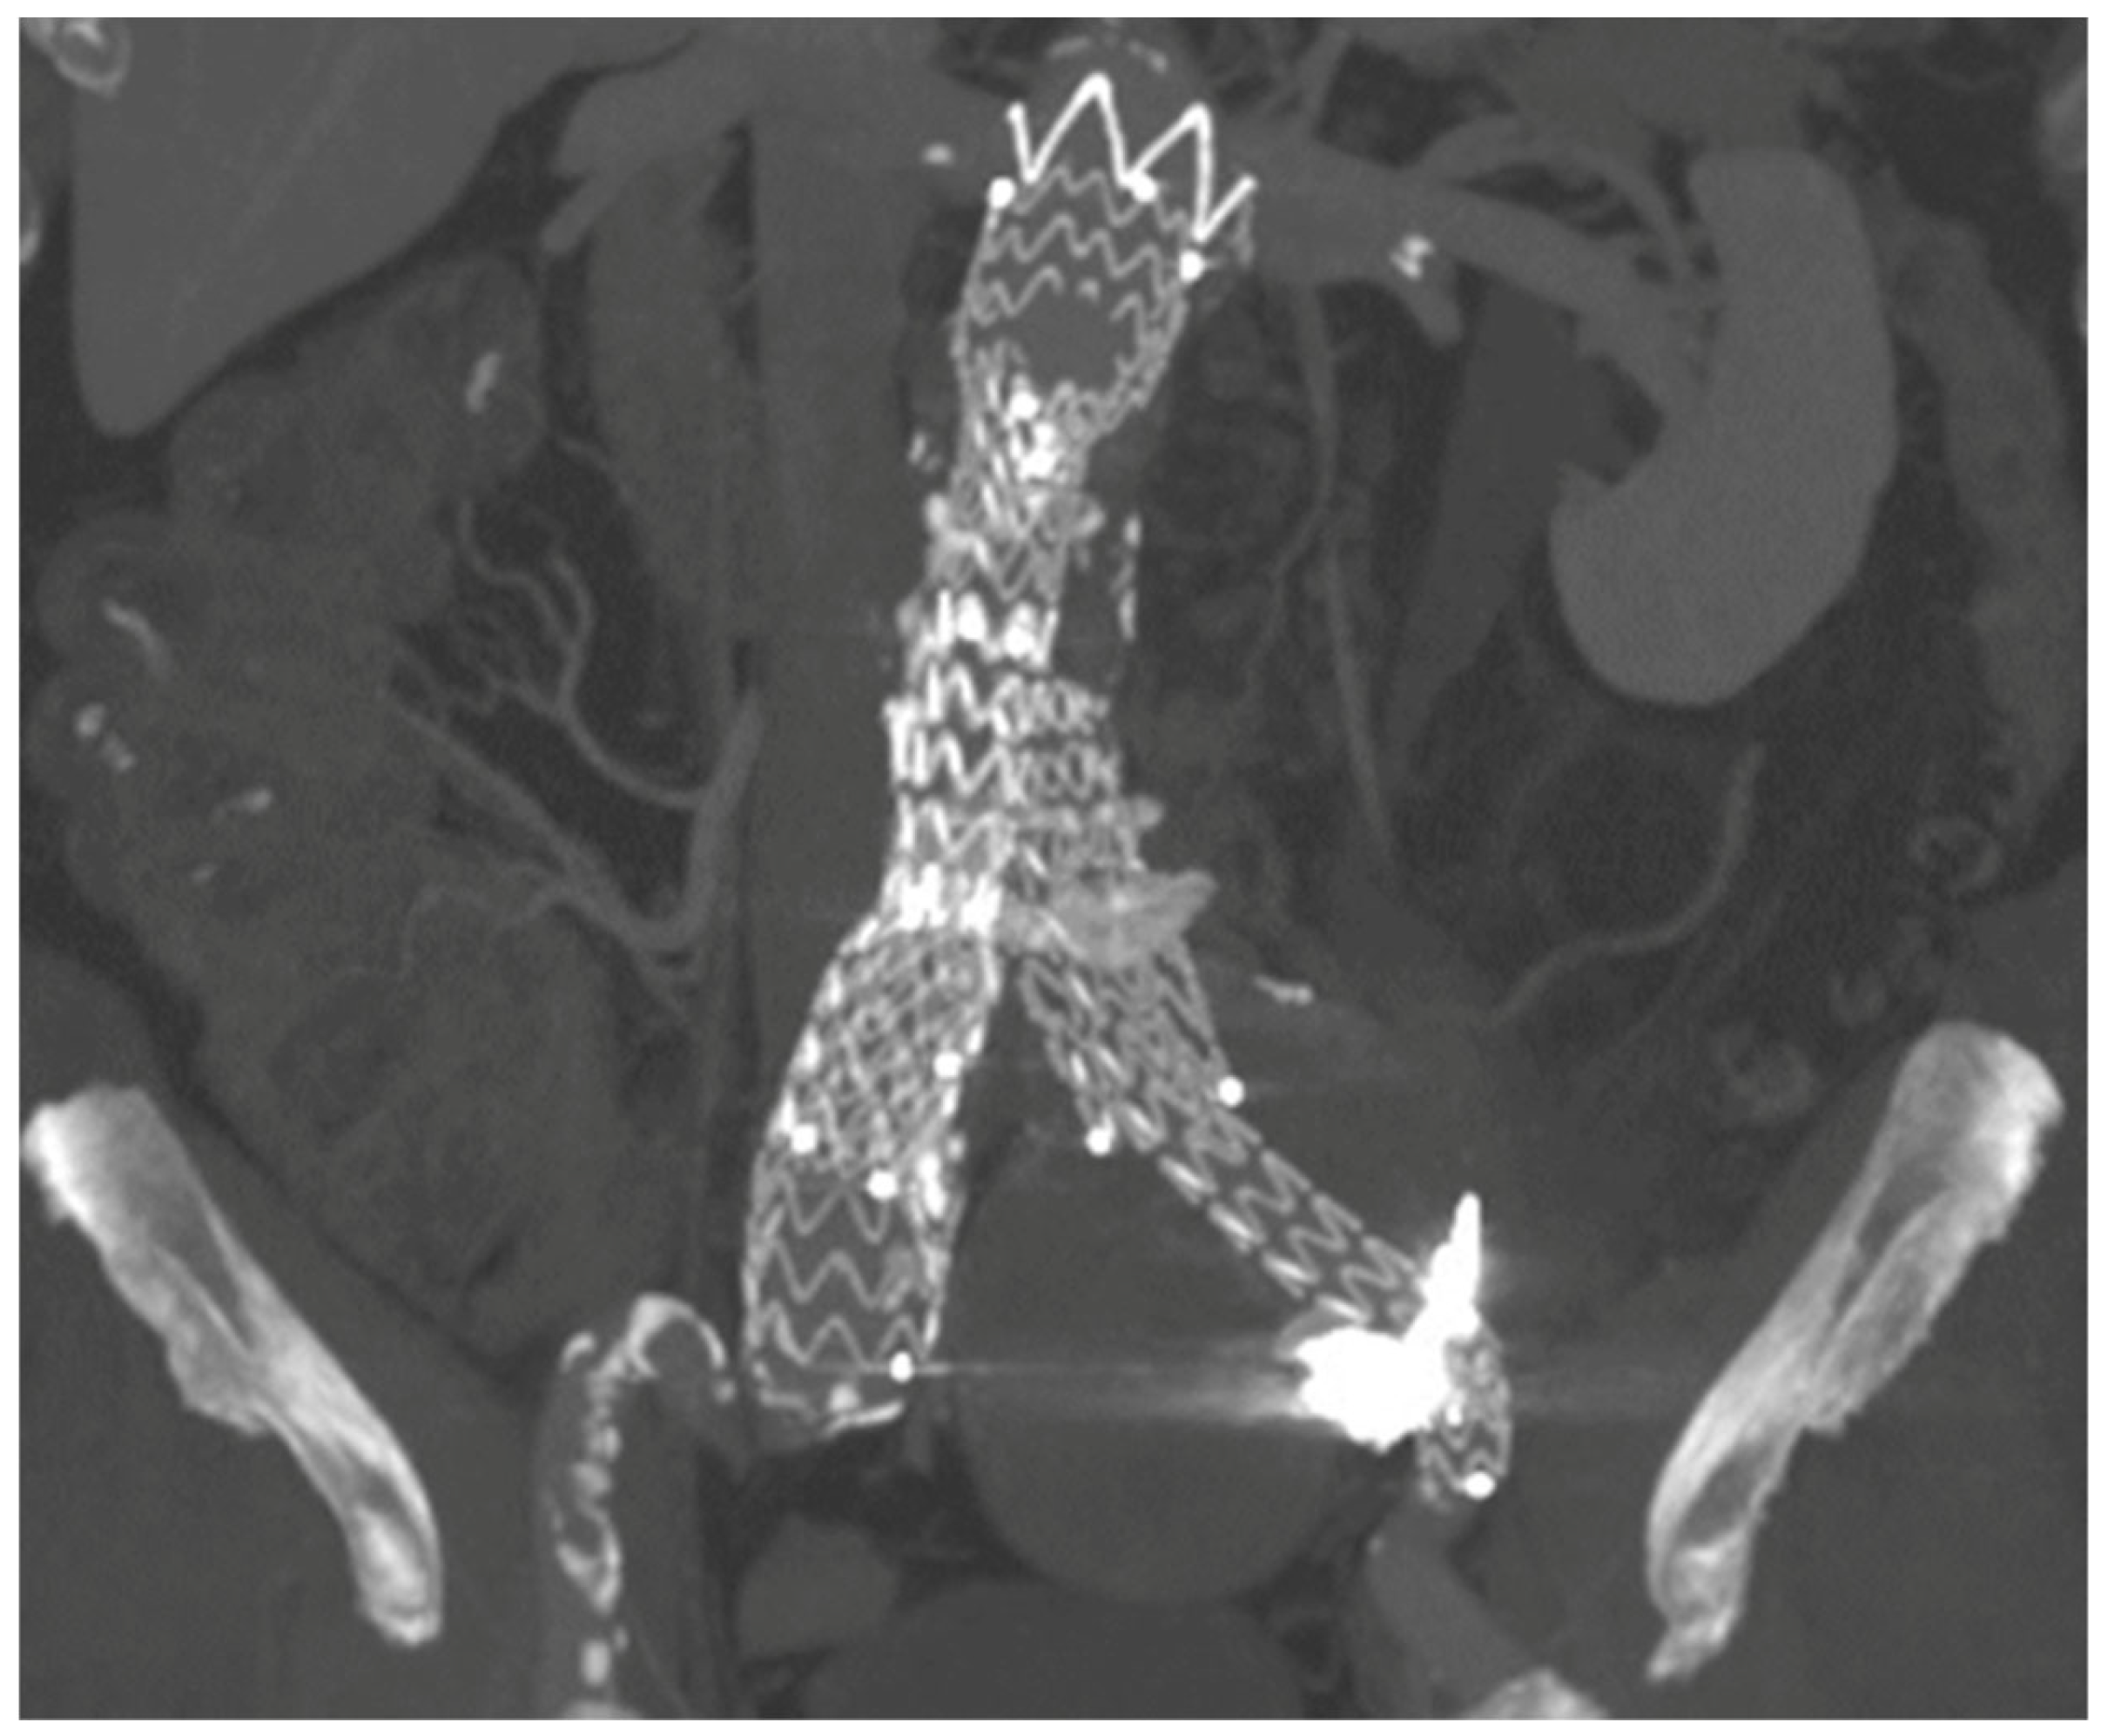

| Present case | Angiographic + DUS guided, 18G needle, sheathless |

Sac embolization with coils and liquid embolic agent | Manual compression | None | 12-months CT-scan, stable sac |